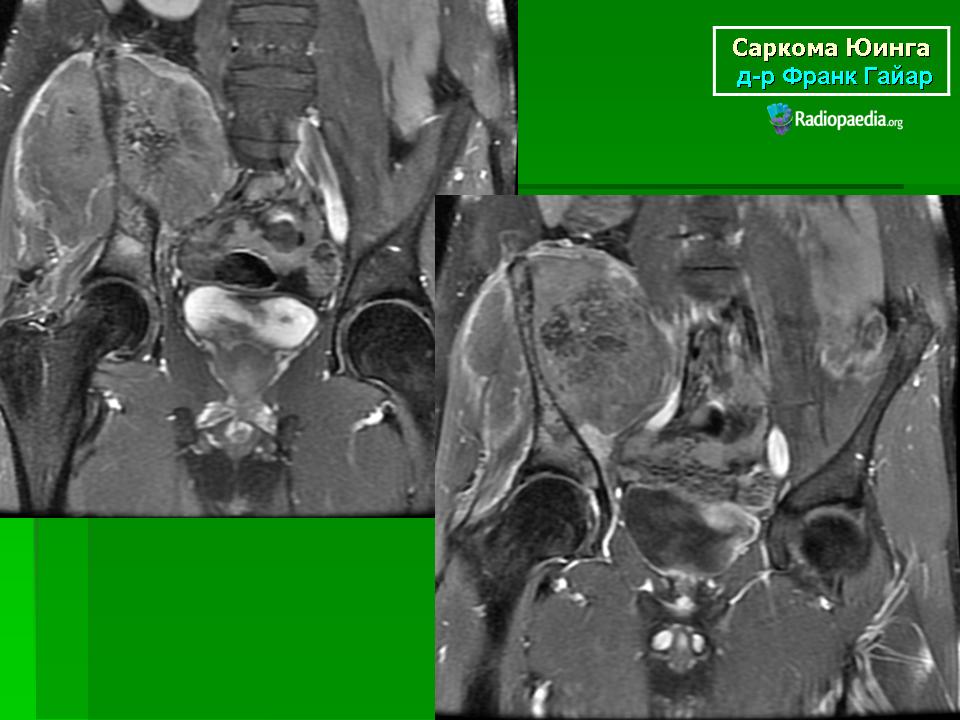

Для установления окончательного диагноза пациенту проводят компьютерную томографию или магнитно-резонансную томография костей и мягких тканей. Кроме того, выполняется ряд исследований для точной оценки характера новообразования.

Данные исследований КТ и МРТ позволят специалистам точно определить размеры новообразования, степень распространенности и поражение близлежащих тканей.

При выявлении типичных рентгенологических признаков саркомы Юинга больного направляют в отделение онкологии, где проводится расширенное обследование для оценки состояния первичного очага и выявления метастазов. В ходе такого обследования выполняется компьютерная томография или магнитно-резонансная томография костей и мягких тканей, пораженных злокачественным процессом.

Данные исследования позволяют точно определить размер новообразования, степень его распространения по костно-мозговому каналу, связь с сосудисто-нервным пучком и окружающими тканями.

Магнитно-резонансная томография (МРТ) дает дополнительную информацию относительно состояния костного мозга, мышц и соединительной ткани вокруг пораженных костей и помогает определить степень распространения опухоли.